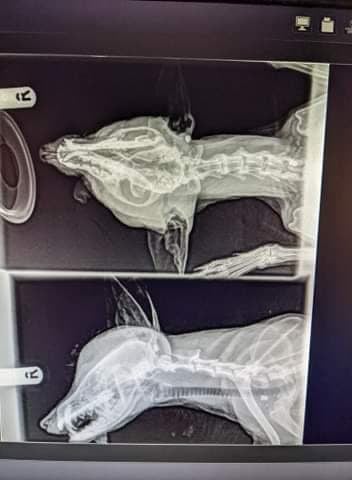

When they arrived, they found that the fox had severe wounds to the head and was missing an eye. The fox was quickly passed to the care of Kent Wildlife Rescue Service, who confirmed via X-Ray that the fox had been shot twice in the head. It was their opinion that the fox was potentially shot by a more powerful firearm than a pellet gun.